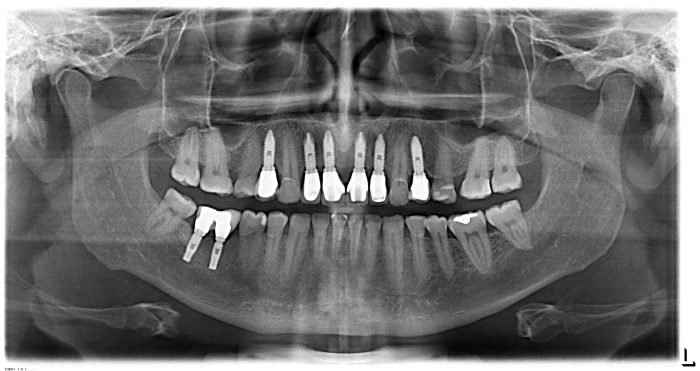

Imagem inicial